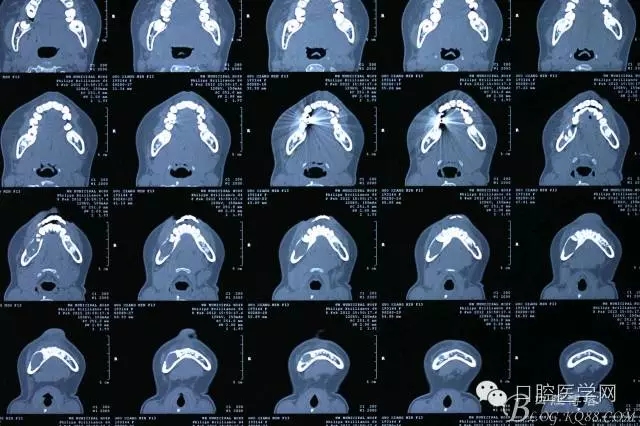

查:右側(cè)第二前磨牙第一乳磨牙恒尖牙頰側(cè)前庭溝隆起,捫有乒乓球感。曲斷及CT示:右側(cè)第二前磨牙第一乳磨牙恒尖牙根尖區(qū)有一囊腫,頰舌側(cè)骨板極薄,牙根無吸收,第二前磨牙牙根位于囊腫中,第一雙尖牙牙冠遠(yuǎn)中水平向阻生,牙冠位于囊腫中。經(jīng)協(xié)議:手術(shù)摘除創(chuàng)傷大,同意開創(chuàng)引流保守治療。

術(shù)后一個月 三個月 五個月 八個月 拔除第一雙尖牙后 曲斷片: